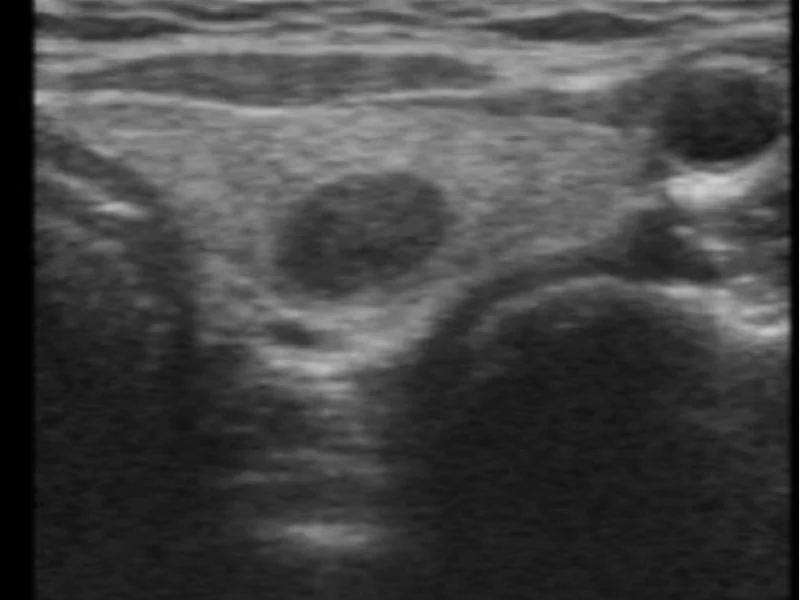

- Ultrassom se houver nódulos